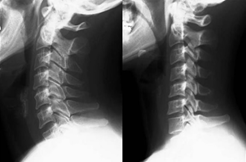

1.ストレートネック

頸椎の生理的前湾角度(第1頸椎椎体と第7頸椎椎体のなす角度)が30°以下の首をストレートネックと呼びます。

うつむき姿勢を取ることにより、首の生理的なカーブが失われ、ストレートネックになります。長時間のパソコン作業やスマートフォンやゲームは最も代表的な原因です。

3.変形性頚椎症・頚椎症性神経根症

椎間板の退後変性に基づき、椎間板腔の狭小化・椎体辺縁の骨棘形成・椎間関節の狭小化により、首の動きを悪くしたり、痛みを誘発します。

頸椎の変化は主に加齢や外傷が原因で起こります。加齢による頸椎の変化には個人差がありますが、一般的には40歳ごろから明らかになります。

高齢になるほどその変化が強くなるため、頸椎症は中高年者で多く発症します。